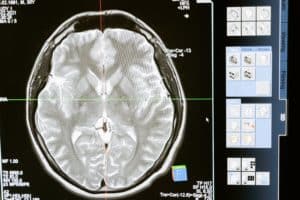

Brain Function

B12 is also extremely important for brain function. A lack of it can result in cognitive impairment and brain atrophy (or shrinkage of the brain). The brain atrophy leads to significant memory loss and dementia.